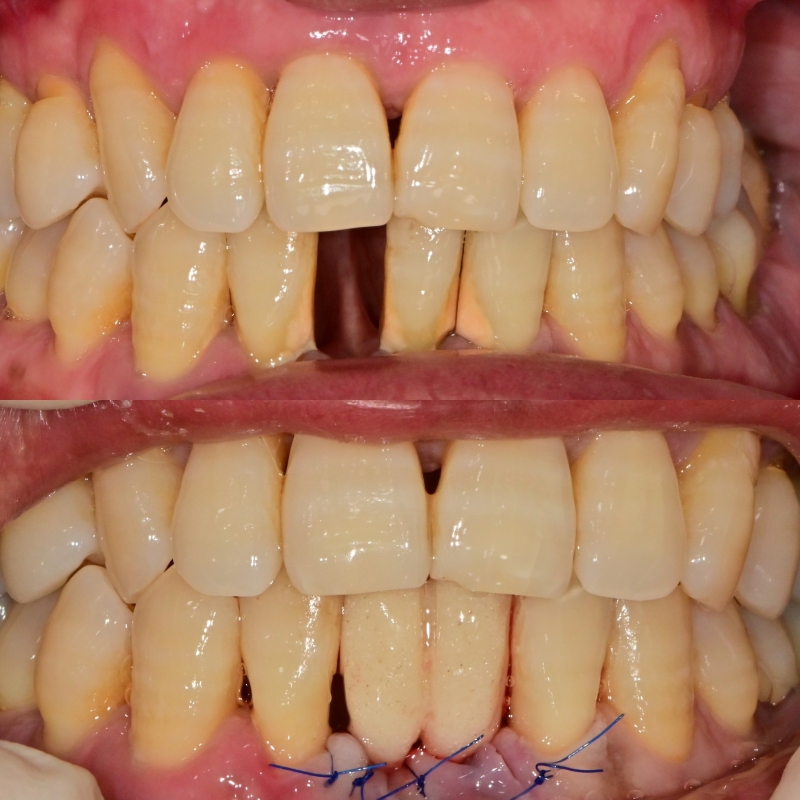

임시치아를 이용한 임플란트 수술 후 즉시 고정

환자분께서 한 개의 치아는 자연 발치된 상태에서 내원해 주셨습니다.

전반적으로 치주가 안 좋은 상태였고, 바로 옆 치아도 발치가 필요한 정도로 좋지 않았습니다.

환자분께서는 앞니 임플란트 수술을 하더라도 빈 공간은 빨리 채우고 싶다고 하셨습니다.

위 경우 임플란트와 주변 뼈의 초기고정이 나쁘지 않았기 때문에 이런 식으로 임시치아를 이용한 즉시 회복이 가능했습니다.

일반적으로 임시치아를 사전제작 후 수술에 들어가지만 시간이 없는 관계로 수술 당일에 진료체어 옆에서 즉시 제작해서 완성했습니다.

고정성의 임시치아의 경우 임플란트가 주변골과 결합이 충분히 되는 (osteointegration) 과정까지 충분히 기다려야 되는 기간 동안 빈 공간과 주변 잇몸의 회복을 용도로 사용되고, 주의할 점은 해당 기간 동안 절대 앞니에 자극을 주거나 식사를 하는 행동을 피해 주셔야 합니다.